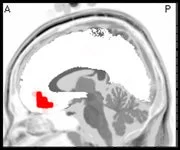

What is missing from the record is any organized, dominant alpha pattern—normally seen during an eyes closed recording. For adults, the alpha peak frequency is normally around 10hz. The following spectra graphs show where the alpha peak would be, if it were present. Additionally, the Z score (statistical) spectra graph shows a dip instead of a peak, further accentuating the absence of a normal alpha pattern.

Attenuated alpha has been shown to be associated with anxiety in some persons, and may be a marker for emotional trauma. However, the automated report fails to register this pattern. No protocol is recommended by the report for addressing this issue. Eyes closed, posterior alpha training has been found to be helpful for these individuals.